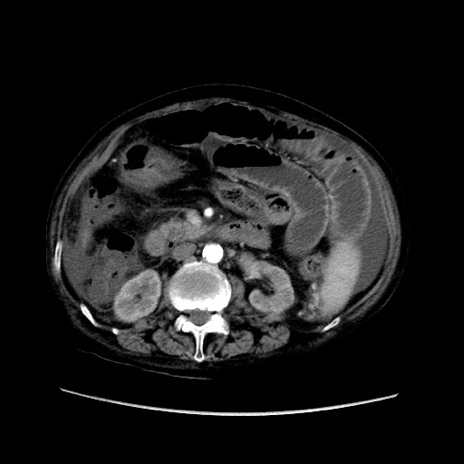

症例31(横断像)

【症例】80歳代 女性

【主訴】腹部膨満感

【現病歴】他院にて肝硬変にてフォロー中。1週間前から便秘、腹部膨満感、臍部腫瘤あり受診となる。

【既往歴】肝硬変

【身体所見】腹部膨隆あり、皮膚変化なし、疼痛なし。

【データ】WBC 4600、CRP 0.25